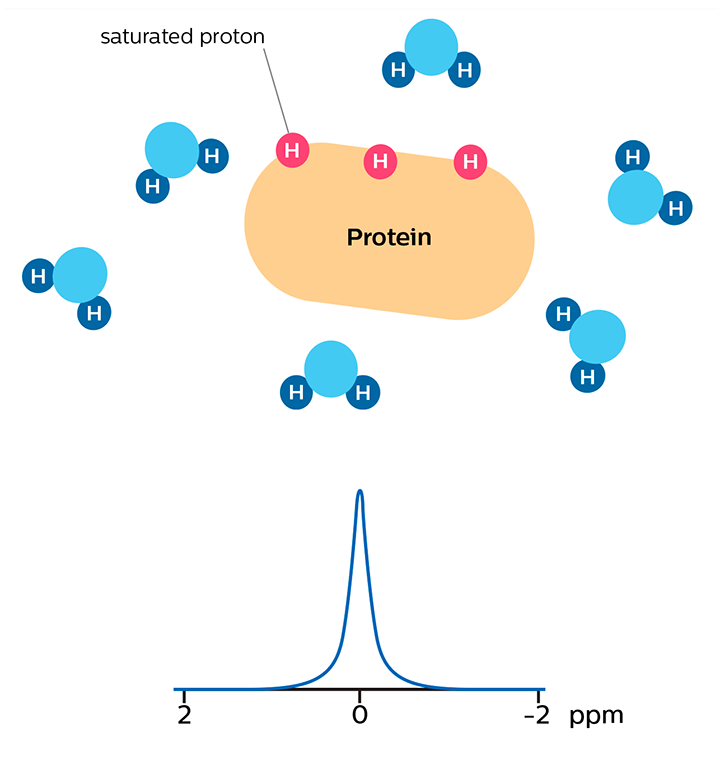

In APT weighted imaging and other CEST methods, the MRI signal is generated by a mechanism different from that of basic MRI. These CEST techniques are based on the chemical exchange of hydrogen atoms. The signal of amide protons of peptide bonds in proteins is too low to be measured in normal MRI. The hydrogen (proton) exchange between protein amide groups and surrounding water allows a different way to measure these amide protons. In APT a narrow RF prepulse (saturation pulse) at the amide hydrogen’s frequency is given to attenuate its MR signal. Because the amide group and water continually exchange hydrogen atoms, the number of saturated protons will build up in water, so that the measured water signal will become lower. The change of the MRI signal of water provides an indirect way to measure the presence of amide. APT images are usually presented as color maps, created by using an asymmetry calculation so that presence of APT is shown as a positive colored signal.

Saturation prepulse on protein's amide proton frequency nulls MR signal of these protons

MR signal of water is high